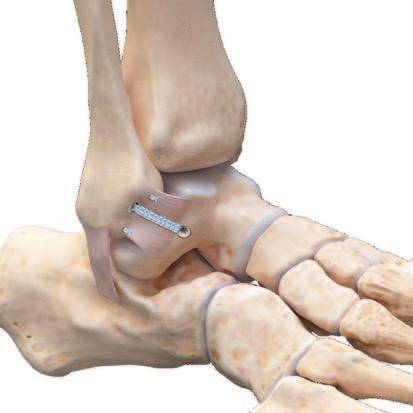

The authors’ current surgical approach to repair of the UCL includes the standard medial incision just posterior to the medial epicondyle (Figure 1). The cubital tunnel is exposed, and the ulnar nerve is dissected out both proximally and distally. The ulnar nerve is transposed to decrease the rate of post-operative ulnar neuritis.20 The sublime tubercle and medial epicondyle are then identified. For UCL expo sure, a muscle-elevating approach is used to elevate the flexor-pronator musculature off the anterior band of the UCL.13,21 With full exposure of the ligament, the anterior band is split in line with its fibers in order to access and de bride a proximal or distal avulsion. Once completed the in ternal brace, which was prepped on the back table, is placed through a 3.5 mm SwiveLock (Arthrex Inc, Naples, FL) with a 2-0 nonabsorbable suture for repair

The drill guide is then inserted either on the center of origin of the UCL at the medial epicondyle for proximal tears or the anterior aspect of the sublime tubercle for dis tal tears.22 The first anchor of the internal brace is placed appropriately and the limbs of the nonabsorbable suture are passed through the ligament’s anterior and posterior bands and tied in simple fashion to complete the repair The remaining FiberTape (Arthrex Inc, Naples, FL) is then loaded through a second 3.5 mm SwiveLock. A similar drilling and taping process is performed on either the re maining proximal or distal end of the ligament. The lon gitudinal split in the ligament is then closed with an in terrupted 0 vicryl. The FiberTape is tensioned as to not supersede the native tension of the ligament and the an chor is provisionally inserted as the arm is taken through a full range of motion to confirm reduction of the joint with adequate tensioning and isometry on the graft, ensur ing there is no non-physiologic constraint of the repaired UCL. The 3.5 SwiveLock is then inserted until the anchor is seated. Finally, interrupted 0 vicryl sutures are placed around the native ligament and around the internal brace to supplement fixation and prevent windshield wipering of the brace itself (Figure 2). The ulnar nerve is transposed an teriorly and secured under two fascial slings with 3-0 ticron and the internal brace is complete (Figure 3a/b).